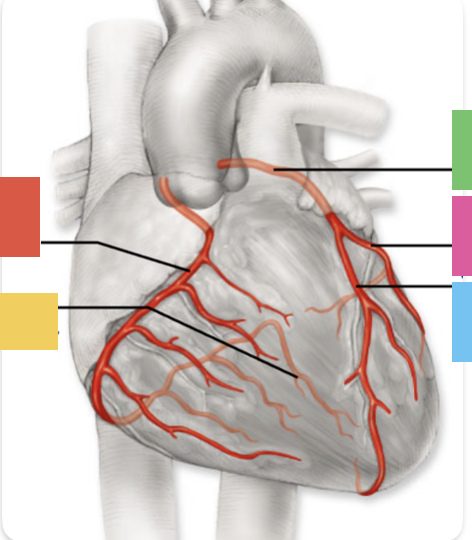

red

right coronary artery

yellow

posterior interventricular artery

green

left coronary artery

blue

anterior interventricular artery

pink

circumflex artery

coronary sinus